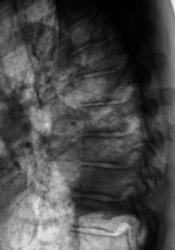

Произведено дообследование.

Рентгенография и томография.

Осумкованный пристеночный плеврит.

Пропунктировали, согласились "на осумкованный плеврит".

Похоже на осумкованный, или как?